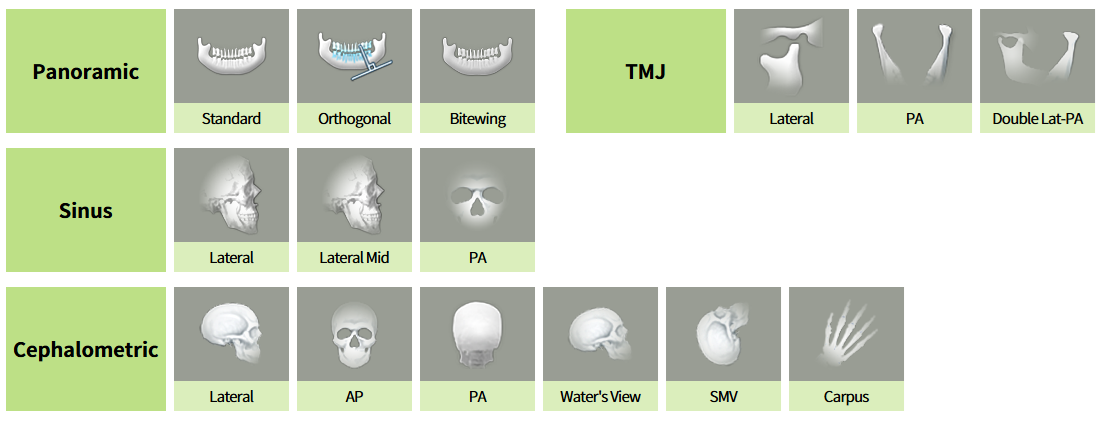

Különféle szkennelési módok

A panoráma-, CT- és cefalometriai* szkennelési módok segítségével pontos diagnózis állítható fel.

*opcionális